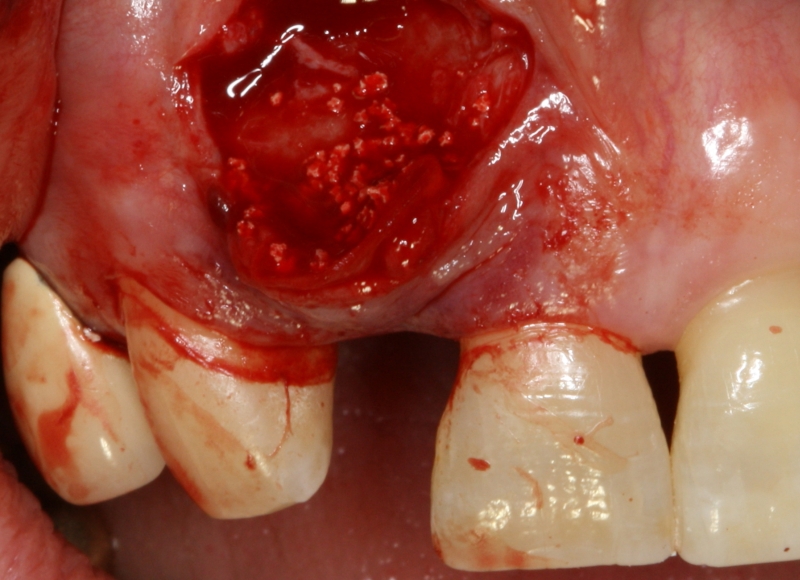

08/20 - Surgical presentation of the alveolar ridgeGBR with maxresorb® & Jason® membrane - Prof. Dr. Dr. D. Rothamel